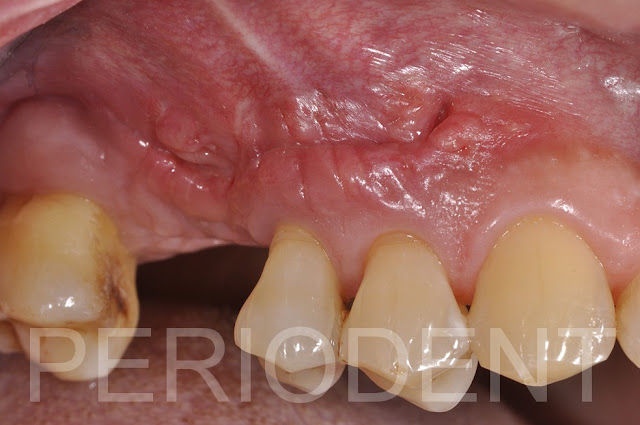

拆線時